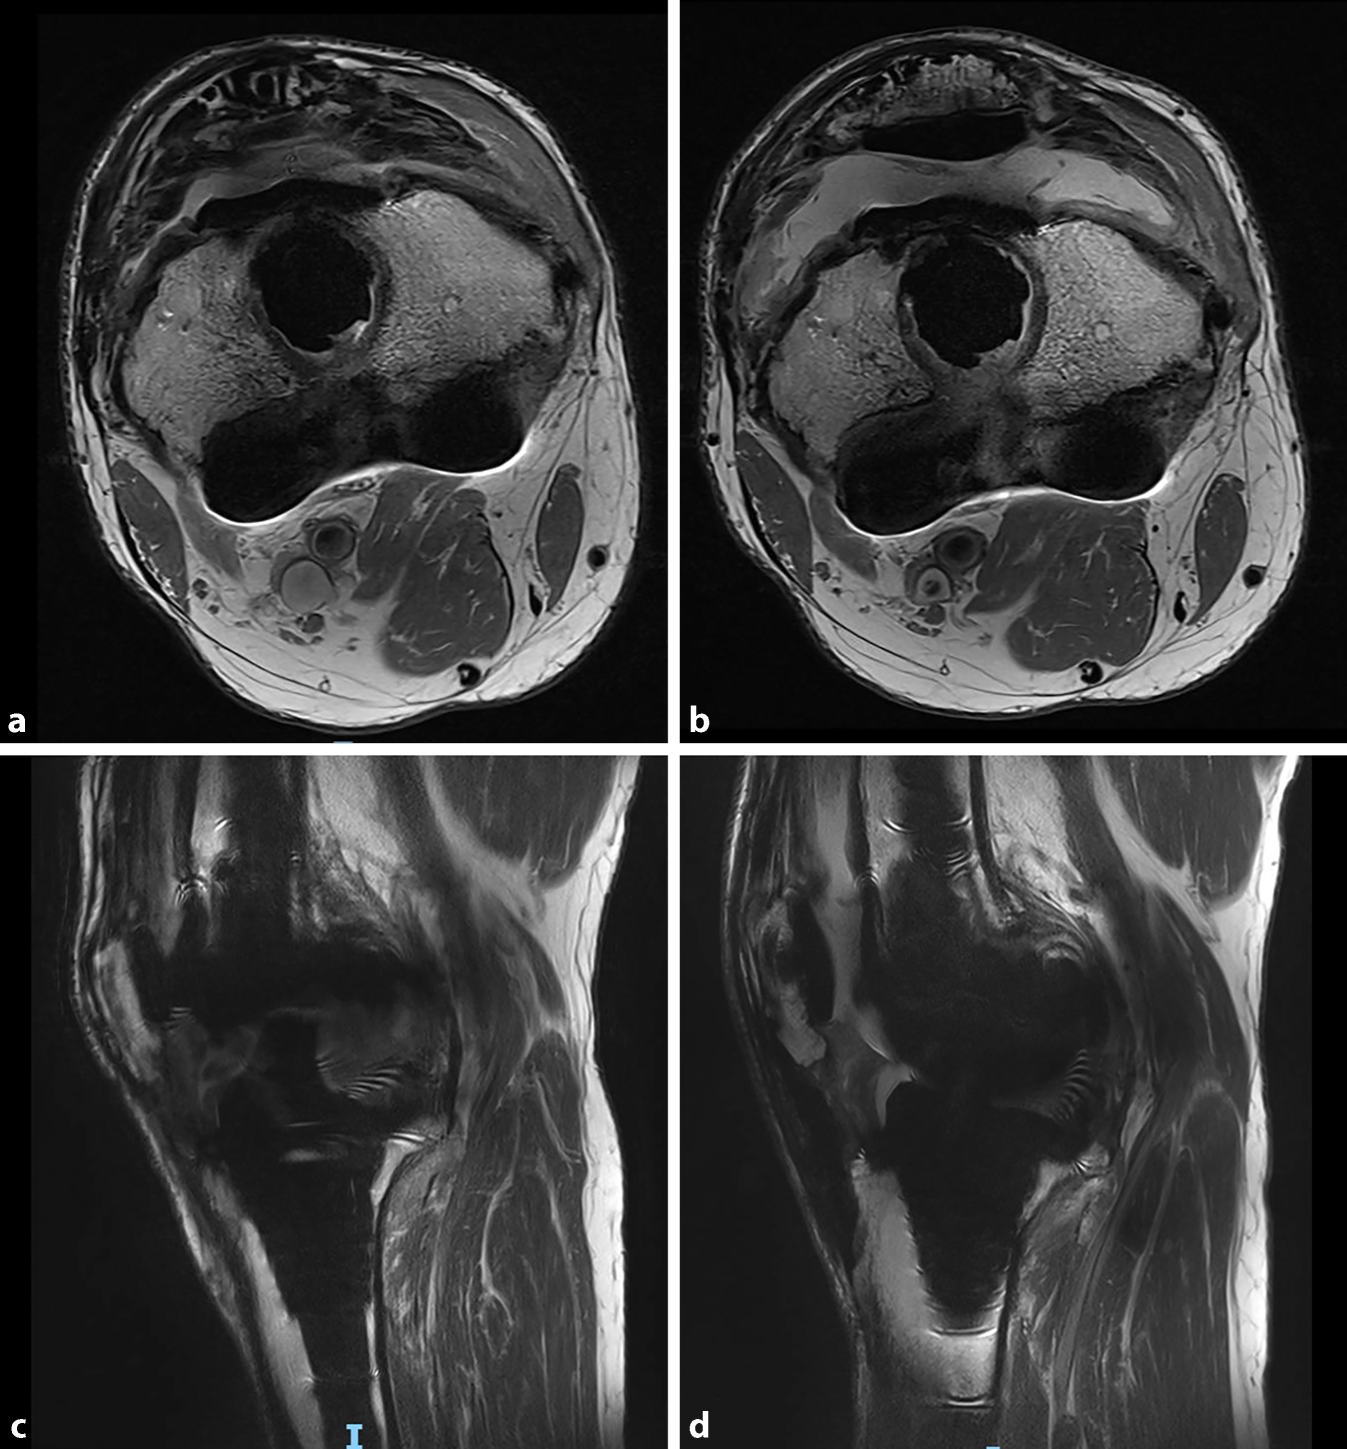

Die Metallartefakt-unterdrückende MRT (MARS) ist in der Lage, die intraartikuläre Narbenbildung exakt zu vermessen (Abb. 7). Es können eine Hypertrophie der Synovialmembran sowie intraartikuläre Adhäsionen nachgewiesen werden [28, 55, 56]. So konnten Attard et al. [55] eine Arthrofibrose-assoziierte Verdickung der Synovia um ca. 2 mm im Vergleich zu unauffälligen Knieprothesen nachweisen. Aufgrund der zunehmend besser werdenden Bildqualität ist die MRT heute eine sinnvolle ergänzende Bildgebung bei Patienten mit postoperativer Gelenksteife.

Abb. 7

Metallartefakt-unterdrückende Magnetresonanztomographie (MARS), Knie links prä- und postoperativ nach arthroskopischer Arthrolyse. a Präoperativ axial, b präoperativ sagittal, c postoperativ axial, d postoperativ sagittal